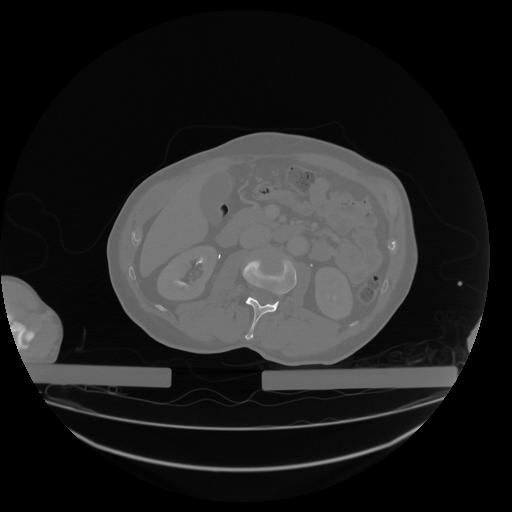

34 CUERPO,CE,Vol,1.0,CUERPO,,